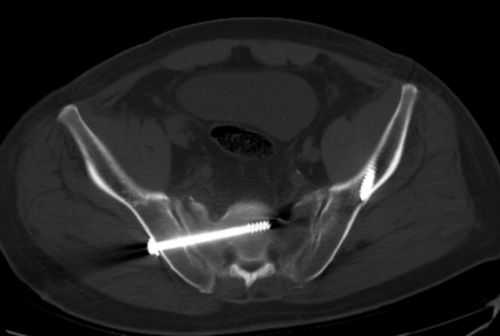

术后复查ct显示:骶髂螺钉固定位置良好。

盛斌主任及其团队反复研究后,于412日为患者施行骨盆微创经皮骶髂螺钉和Infix内固定手术治疗复杂骨盆骨折,并采用微创经皮椎弓根钉撑开复位内固定手术治疗腰椎骨折。术中仅用三个1.52cm的小切口就完成骨盆骨折微创手术操作,出血不到10ml,手术仅耗时30分钟。

“微创经皮骶髂螺钉和Infix内固定是目前较先进的微创手术方式,国内只有大型三甲捷克论坛 可以开展”,盛斌表示,该手术方式技术要求高,如固定不当,易损伤毗邻的重要血管、神经或脏器组织。捷克论坛 岳麓山院区采用最先进的术中滑轨CT,极大地提高了手术的准确性与安全性。